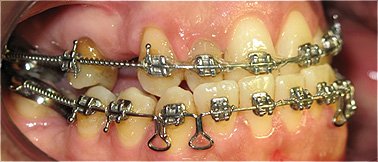

Apinhamento dentário com os dentes caninos em desoclusão (classe II, divisão 2).

![]() |

Após dois anos de tratamento ortodôntico.